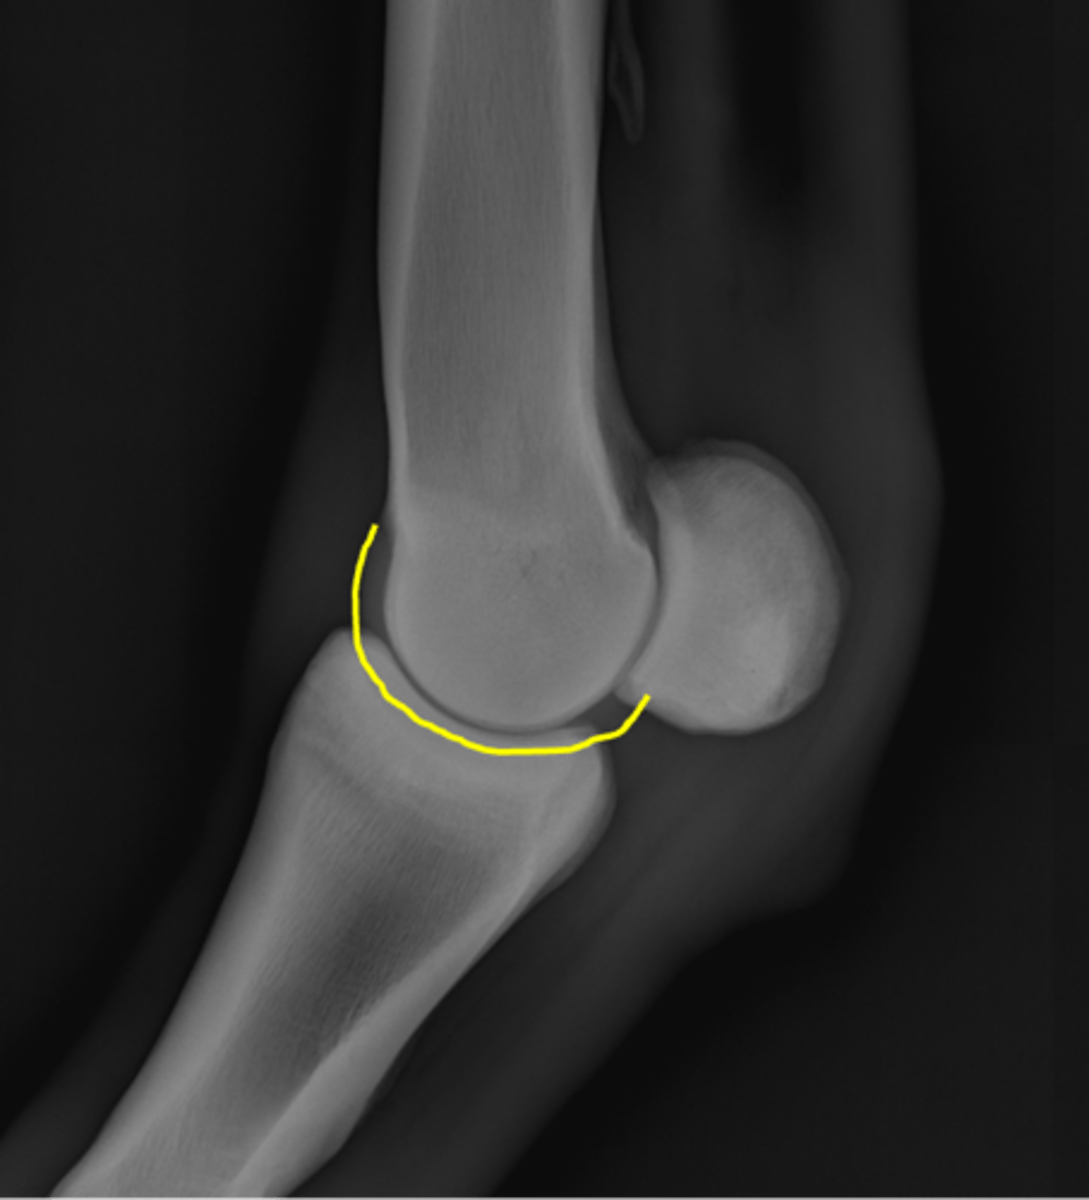

Proximal sesamoid bone

Sagittal ridge

Condyles of third metacarpal bone

Palmar process of P2

Proximal sesamoid bones

Sagittal ridge

Attachment of collateral ligaments

Proximal sesamoid bones

Palmar process of P1

Condyles of the third metacarpal bone